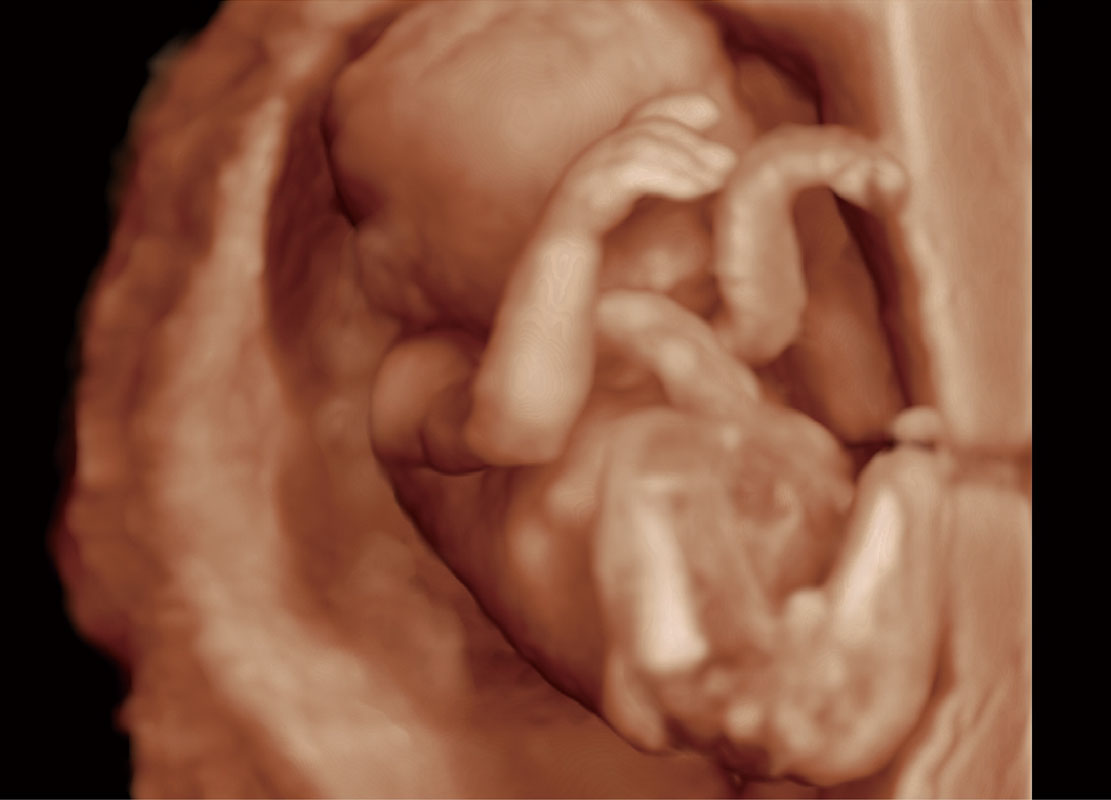

高分辨率容积成像-早孕胎儿

胎儿体循环

光影成像-孕囊